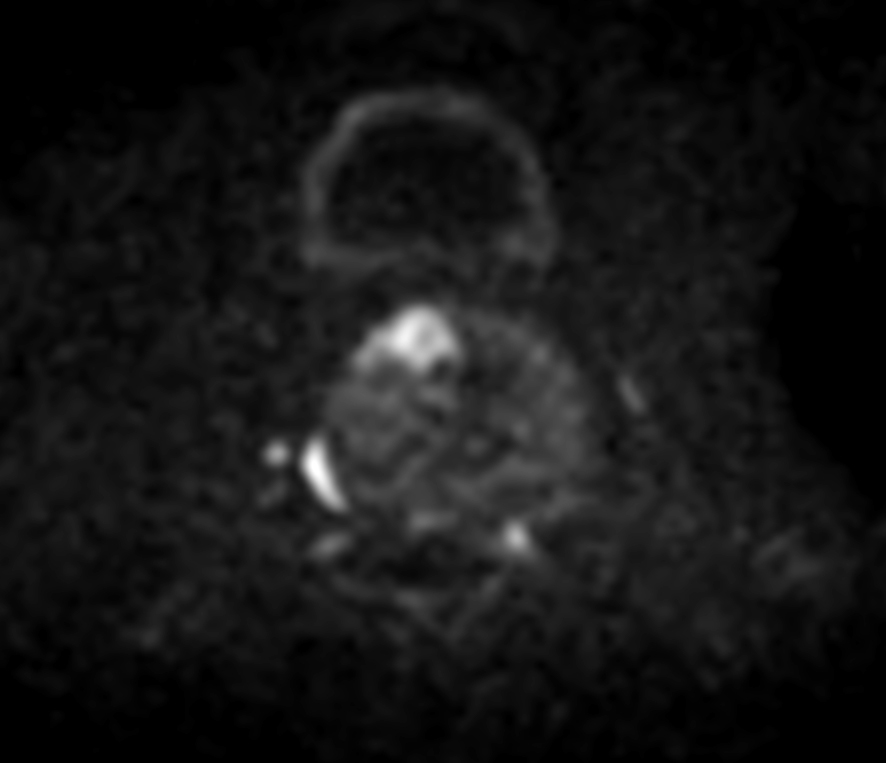

Axial DWI (b100)